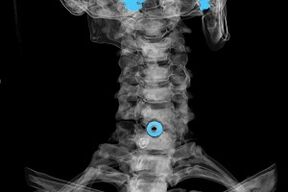

Diagnosticul se face pe baza simptomelor caracteristice și pe baza:

- raze X. Metoda este ineficientă, mai ales în etapele finale ale dezvoltării osteocondrozei.

- RMN (imagistica prin rezonanță magnetică) a coloanei cervicale. O metodă care vă permite să vedeți structurile osoase, hernia de disc, dimensiunea și direcția lor de dezvoltare.

- Tomografia computerizată. O soluție mai puțin eficientă decât RMN deoarece prezența și dimensiunea herniilor sunt greu de determinat.